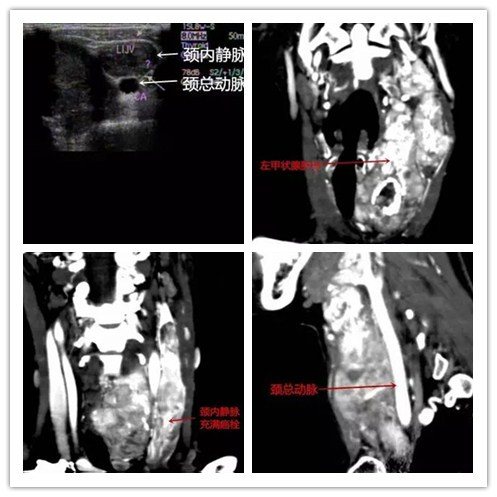

今年3月,患者前来我院就诊。经颈部彩超,发现左甲状腺肿块包饶颈内静脉、颈总动脉,颈内静脉扩张1.6cm,其内充满癌栓,上达颅内,下入胸腔。颈部CT发现左甲状腺肿块向右压偏气管,包裹左颈内静脉,其内血流细微,左颈总动脉通畅,紧贴肿块背侧。经左颈总动脉闭塞试验(BOT),介入导管插入左颈总动脉,造影显示左颈总动脉、左锁骨下动脉正常,肿块血供丰富。扩充颈总动脉内球囊30分钟,观察患者生命体征尚平稳,未出现特殊不适。经我院甲乳外科郑维主任初步诊断为左侧巨大甲状腺癌块并左颈内静脉癌栓及周围组织侵犯(临床III期)。